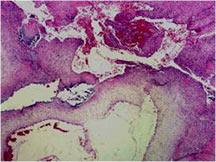

- It is characterized by cystic spaces filled with blood that are separated by thin septa.

- It is a cancerous tumor largely composed of cystic cavities containing necrosis and hemorrhage

- It is postulated that telangiectatic osteosarcomas grow so rapidly that they outgrow there blood supply. Hence portions of the tumor die (undergo necrosis) and form cystic cavities that fill with hemorrhage.

- The cystic spaces filled with hemorrhagic material leads to the presence of fluid-fluid levels on MRIs (so called ABC-like changes or telangiectatic change)

- Tumor has cyst-like spaces divided by septa